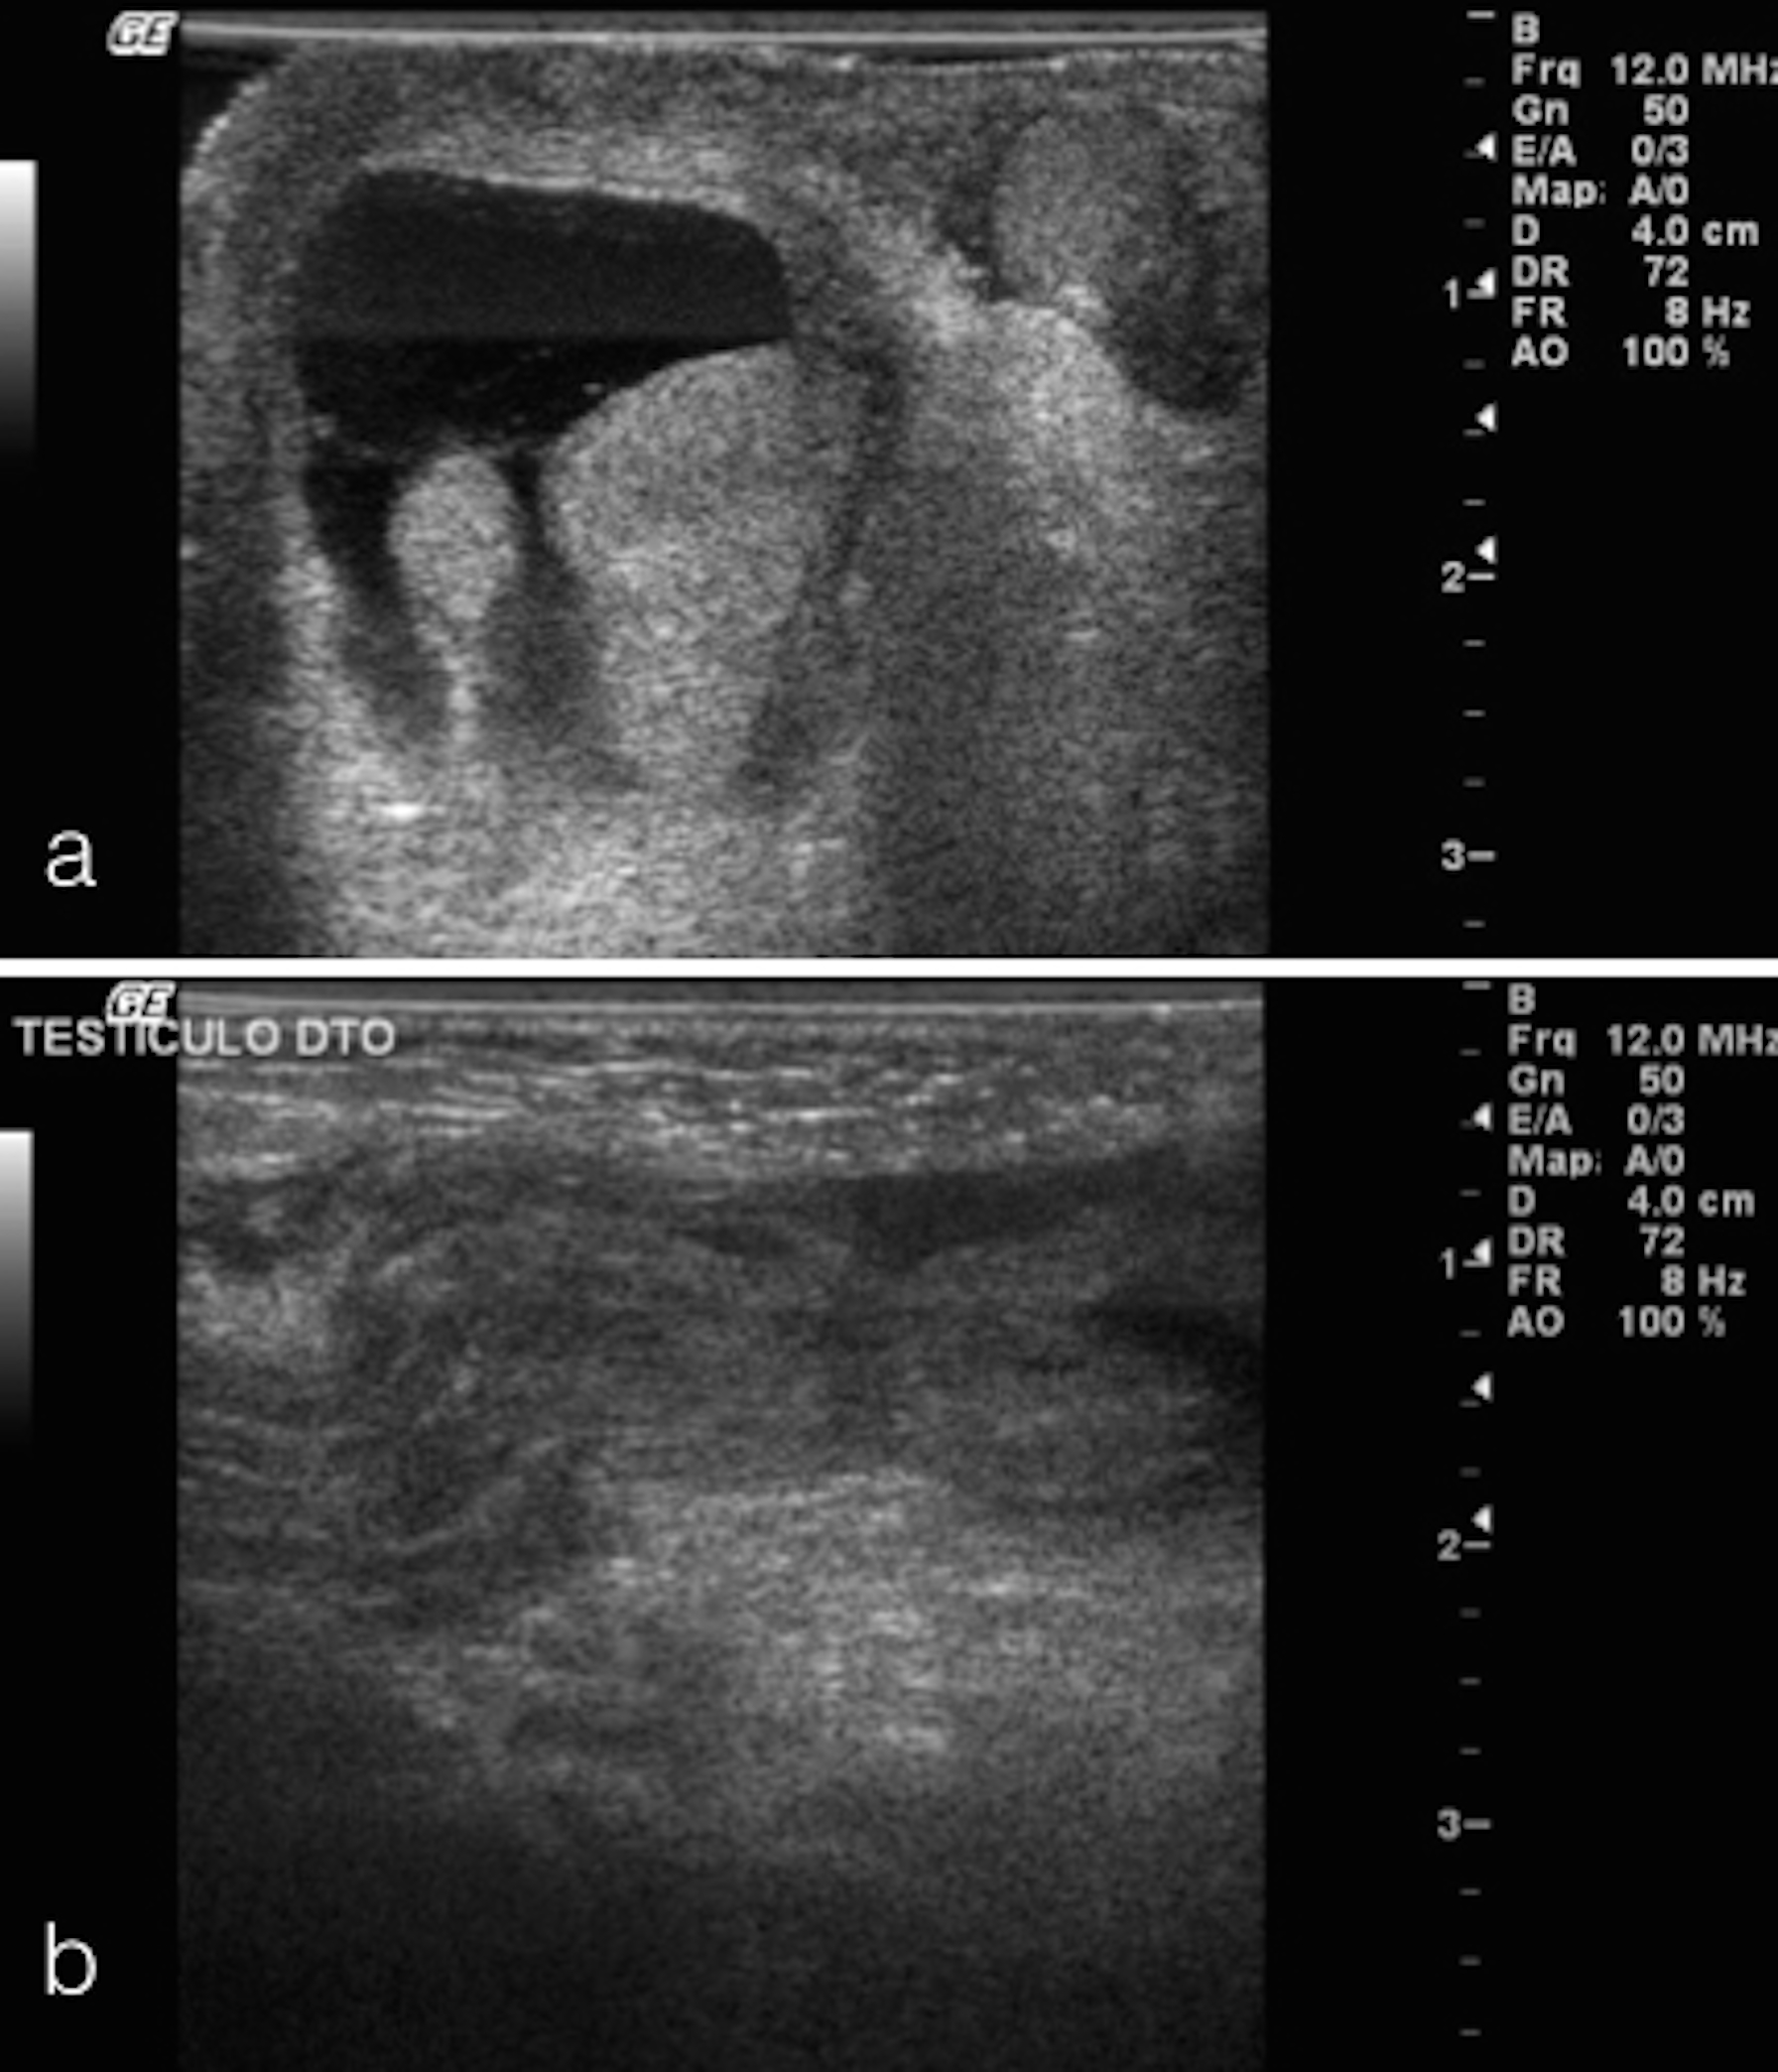

Hematoma escrotal neonatal: um caso clínico

Images in Pediatrics